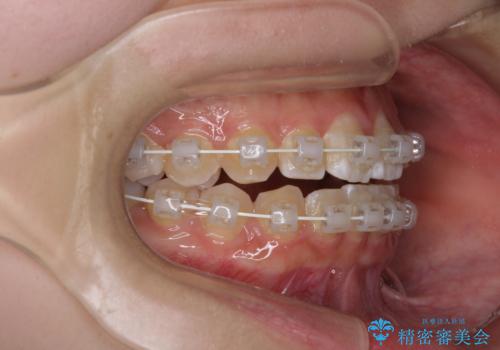

- 前歯のデコボコと磨きにくい奥歯を気にして来院された患者様です。

左右ともに上顎第二大臼歯が外側に転位しており、大変磨きにくくなっているため、補助装置により内側に引き込むことで改善することとしました。

外側を向いていた奥歯は比較的早い時期に歯列に収まり、咬み合わせも磨きやすさも改善することができました。

歯列は元々悪くなかったので、1年ほどで治療を終えることができました。